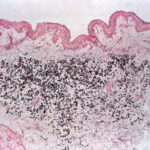

Histopathology. Histologic examination of the involved skin reveals considerable accumulations of swollen and irregularly clumped fibers staining like elastic fibers in the middle and lower thirds of the dermis; that is, they stain deeply black with orcein or Verhoetrs stain . Although normally elastic fibers do not stain with routine stains such as hematoxylin-eosin, the altered elastic fibers in pseudoxanthoma elasticum stain faintly basophilic because of their calcium imbibition. Staining for calcium with the von Kossa method also shows these fibers well. |

In the vicinity of the altered elastic fibers, there may be accumulations of a slightly basophilic mucoid material, which stains strongly positive with the colloidal iron reaction or with Alcian blue . The number of collagen bundles is reduced in such areas, and numerous reticulum fibers are seen on impregnation with silver . In some cases with pronounced elastic tissue calcification, a macrophage and giant cell reaction may be present . |